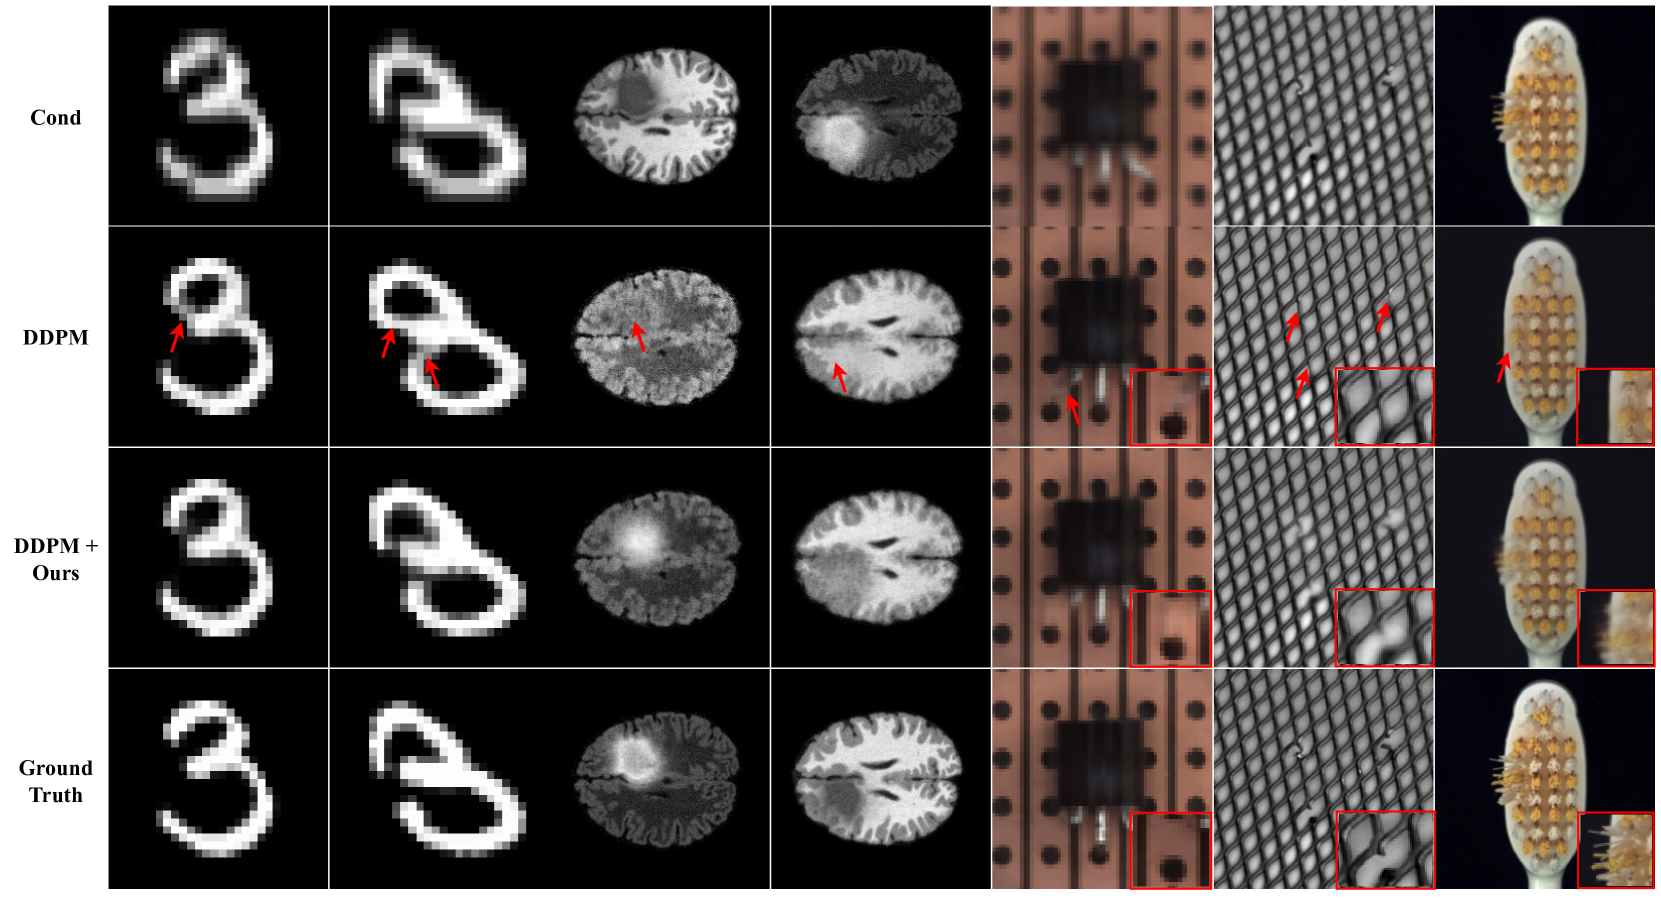

Fig 6 presents a qualitative comparison against DDPM[11], showcasing the effectiveness of our proposed method in reducing structural hallucinations. In the BraTS, predictions generated using DDPM[11] contain hallucinated features, notably misidentifying tumor tissues as healthy white matter. In contrast, our method accurately delineates tumors with appropriate intensity ranges. While the MNIST and BraTS feature relatively large OOD areas, the MVTec dataset comprises different types of OOD with various sizes (e.g., broken leads or grids), posing a challenge for hallucination mitigation. Despite these challenges, our approach demonstrates robust performance on various OOD types, as shown in Fig 6, affirming its effectiveness on various image modalities.

Refer to caption

Figure 6: Qualitative comparison on MNIST, BraTS and MVTec (From top: condition, DDPM[11], DDPM with ours and ground truth). The red arrows indicate structural hallucination.